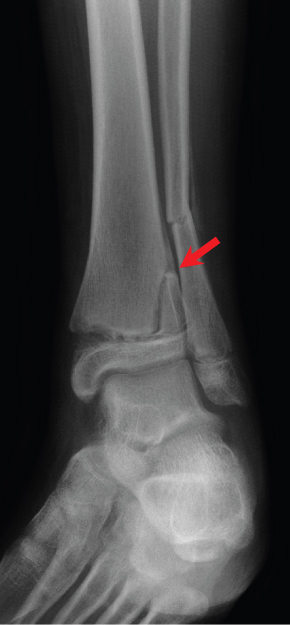

What type of Salter Harris is this?

Type 4 - involves all 3 parts